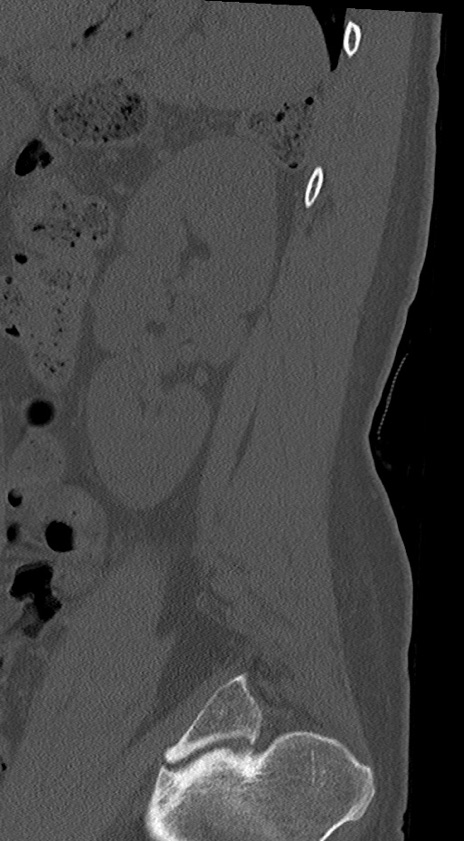

【整形】TIPS症例4 腰椎CT(矢状断像)

腰椎CT

冠状断像